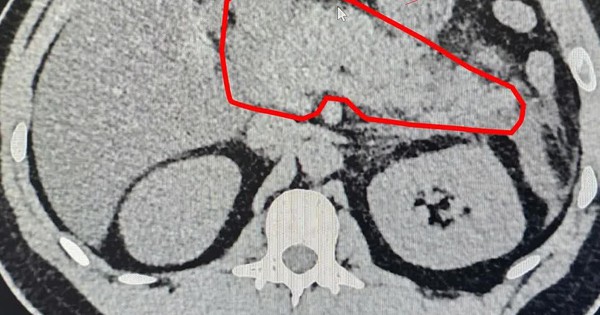

Một bệnh nhân nam 28 tuổi bị viêm tụy cấp nặng do tăng triglycerid máu vừa được Bệnh viện Đa khoa Khu vực Vân Đồn (Quảng Ninh) điều trị thành công.